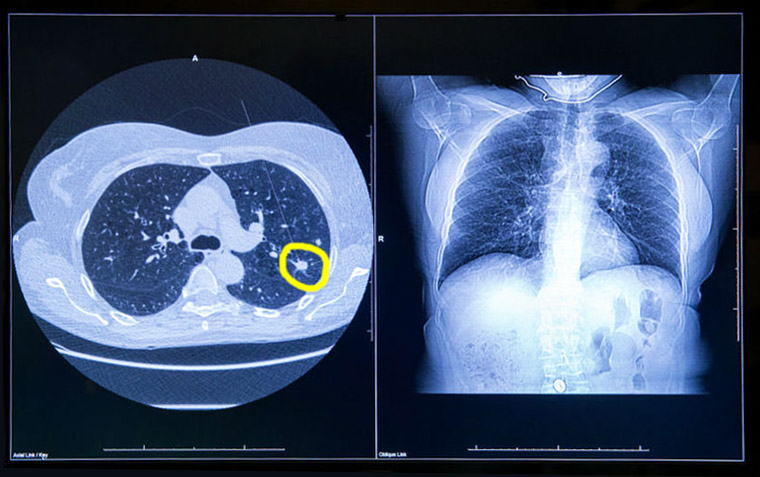

En el estudio danés de tomografía computada de baja dosis para el cribado de cáncer de pulmón se halló que 2 de cada 3 casos detectados podrían corrresponder a sobrediagnóstico. JAMA Internal Medicine, 13 de agosto de 2018

Resultados de la implementación del tamizaje para cáncer de pulmón

La experiencia del rastreo de cáncer de pulmón con tomografía de baja dosis en hospitales de la Administración de Veteranos muestra una tasa elevada de falsos positivos que genera un enorme esfuerzo organizacional. JAMA Internal Medicine, 30 de enero de 2017